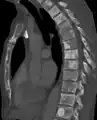

Sclerosis of the bones of the thoracic spine due to prostate cancer metastases (CT image)